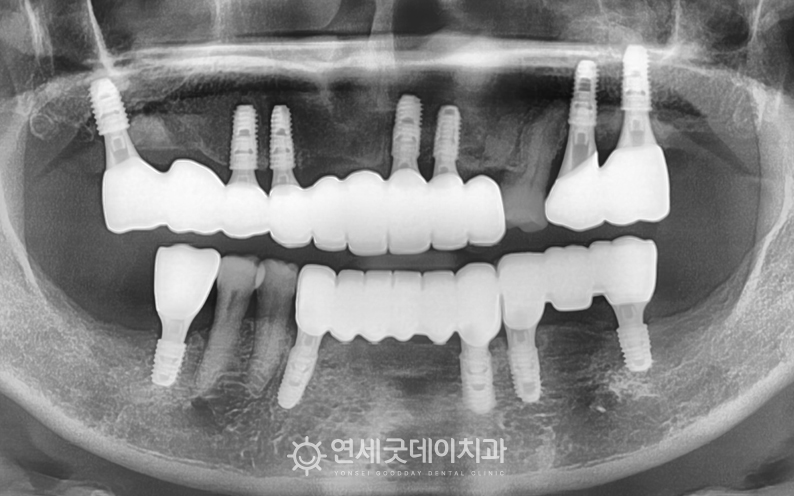

전체임플란트 치료 종결 후 엑스레이 모습 - 급속골이식으로 두꺼운 잇몸뼈 형성 및 브릿지임플란트 연결

▲ 브릿지임플란트 치료 종결

(촬영시기 : 2023년 10월)

골소실 심했던 부위에는 급속골이식을 병행하여 단단하고 뚜거운 잇몸조직이 형성되었고

브릿지임플란트를 통해 전체적인 구강기능과 형태가 재건되었습니다.